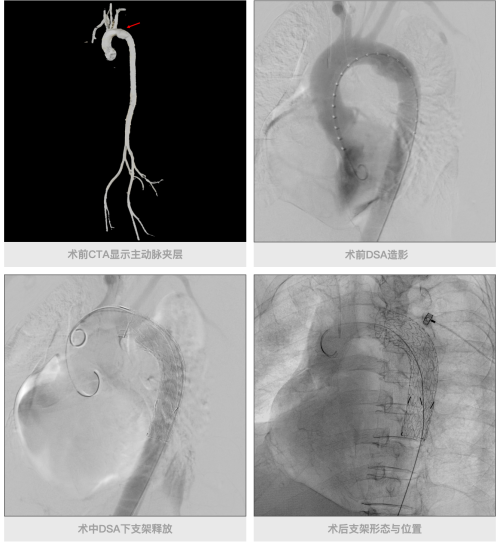

在此次救治过程中,当患者抵达丽水市中心医院后,即刻被送往急诊复合手术室接受CT检查与救治。借助东软医疗NeuViz Epoch +无极系列CT的多Tracker一站式胸痛三联方案,迅速完成了肺动脉、冠脉以及主动脉的扫描。

Debakey Ⅲa型/Stanford B型

该方案采用先进的协议切换技术,基于设备0.235s 的超高转速,能够精准捕捉对比剂在各器官的显影时间窗;搭配特有的多目标追踪扫描技术,支持设置多个检测层,通过阈值触发不同部位的扫描,实现了三个部位血管准确、快速的采集。完成扫描并确诊后,无需转运患者,医疗团队随即使用东软医疗DSA完成了主动脉夹层介入等手术。